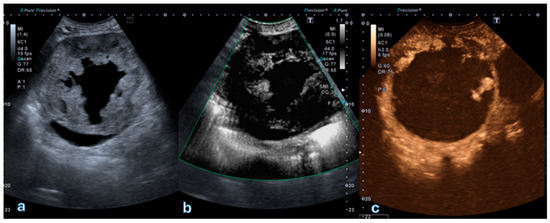

Figure 1

Background and Clinical Significance: Deficiency of Adenosine Deaminase 2 (DADA2) is a rare monogenic vasculopathy characterised by systemic inflammatory and immunodeficiency features. Although neurological and haematological manifestations are well-documented, hepatic vascular involvement remains underappreciated. This report aims to describe the clinical and imaging characteristics of hepatic vascular involvement in a patient with DADA2 and to illustrate the evolution of hepatic lesions during long-term Etanercept therapy. In addition, we provide a synthesis of the available evidence on hepatic manifestations in DADA2, emphasising vascular pathology, clinical presentation, and therapeutic implications. Case Presentation: We describe a girl with early-onset DADA2 presenting with recurrent systemic inflammation, hypogammaglobulinaemia, vasculopathy, and two childhood strokes, followed by the development of multiple FNH-like hepatic nodules on CEUS and MRI with persistently elevated GGT. Genetic testing confirmed biallelic ADA2 mutations, and treatment with Etanercept led to sustained clinical stabilisation and marked regression of liver lesions over a nine-year follow-up period. Her older sister, carrying the same mutations, showed a milder phenotype without hepatic involvement but experienced a mesenteric vascular event. Conclusions: Large regenerative nodules with an FNH-like appearance on CEUS or MRI have not been previously reported in this setting. In our patient, Etanercept therapy produced a favourable hepatic response, reflected by a significant reduction in both the number and size of the lesions. Our case contributes to the understanding of liver disease in DADA2 and the influence of imaging and treatment on the hepatic manifestations of the condition. Full article